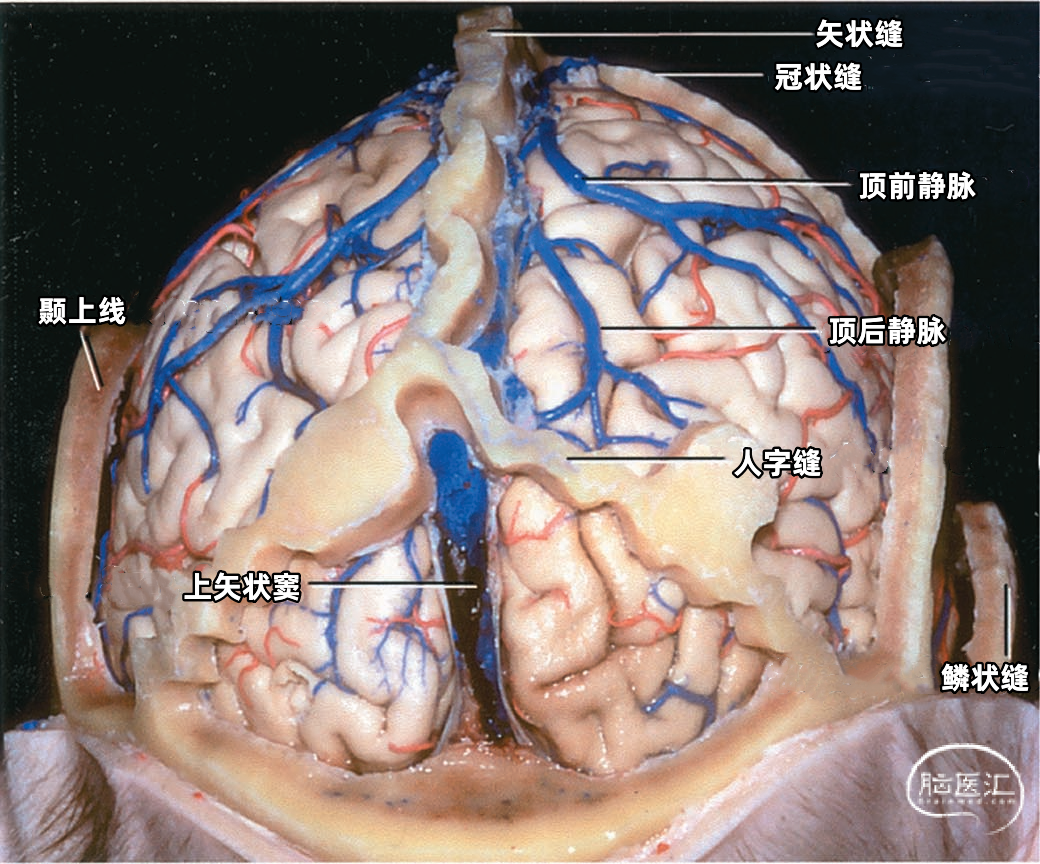

上矢状窦(superior sagittal sinus SSS)位于中线,引流额叶下面的前部和额叶、顶叶、枕叶外侧面及内侧面的上部。 上矢状窦的冠状切面呈三角形,左右两个侧角与覆盖半球凸面的硬脑膜相连接,下角与大脑镰相连。上矢状窦的三角形管腔前部较细,向后逐渐扩大。 上矢状窦两侧壁有的地方向外膨隆扩张,形成外侧陷窝。外侧陷窝常有大脑皮层静脉汇入,还有蛛网膜颗粒突入其中。上矢状窦的下角和外侧陷窝之间常有许多横行的纤维相连。在上矢状窦后部的窦壁内有一海绵状间隙系统,在窦壁内皮与硬脑膜之间,形成海绵状间隙,参与调节脑血流量。

外侧陷窝通常很复杂,几乎呈丛状,很少以简单的中空形式存在。矢状窦、横窦和直窦旁丛状分布的小静脉以及“海绵”静脉组织的脊往往与上矢状窦和横窦的管腔相交通。上矢状窦内也有一些纤维束形成隔将其管腔分为上、下两个通道。

上矢状窦在前方可能通过盲孔与鼻腔的静脉相交通。上矢状窦在枕内粗隆处通过窦汇静脉丛复合体引流入横窦,上矢状窦可均等引流入左右横窦,也可以一侧横窦为主或完全引流入一侧,但一般是右侧横窦接受主要的回流。

从两侧皮层汇入上矢状窦的皮层静脉具有特有的形态(下图)。左侧显示汇入上矢状窦的静脉,右侧显示静脉入窦的平均角度。从前到后,静脉入窦的角度逐渐减小。 额极附近的静脉,与上矢状窦内血流方向一致,汇入上矢状窦; 额叶后部的静脉向前汇入上矢状窦,与窦内血流的方向相反; 顶叶和枕叶的静脉向前汇入上矢状窦,与窦内血流方向相反;| 额极静脉 110° | 额前静脉 110° |

下图示后面观。枕叶的静脉均向前走行进入上矢状窦,因而在人字缝以下的区域(窦汇前4~6cm)几乎没有进入上矢状窦的桥静脉,这就使得手术中将枕叶抬离矢状窦而不需要牺牲任何桥静脉。

下图示右侧中央后静脉、顶前静脉,顶后静脉汇入上矢状窦。没有桥静脉汇入上矢状窦后部。抬起右侧枕叶显露小脑幕,大脑镰和直窦。在枕极和上矢状窦、直窦之间没有桥静脉。